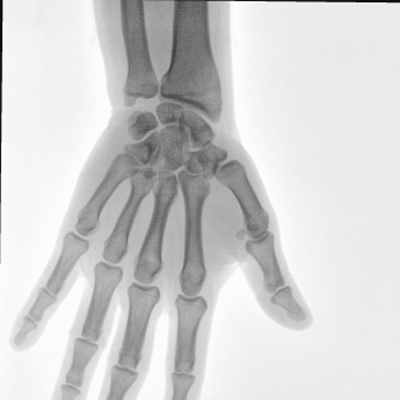

大尺寸動(dòng)態(tài)平板探測器,高DQE、低噪聲、圖像清晰。采用多分辨率圖像增強處理技術(shù),不同部位不同圖像處理算法,滿(mǎn)足客戶(hù)多樣化的需求。

采用智能變頻脈沖透視技術(shù),優(yōu)化圖像質(zhì)量的同時(shí)降低輻射劑量,呵護醫患健康